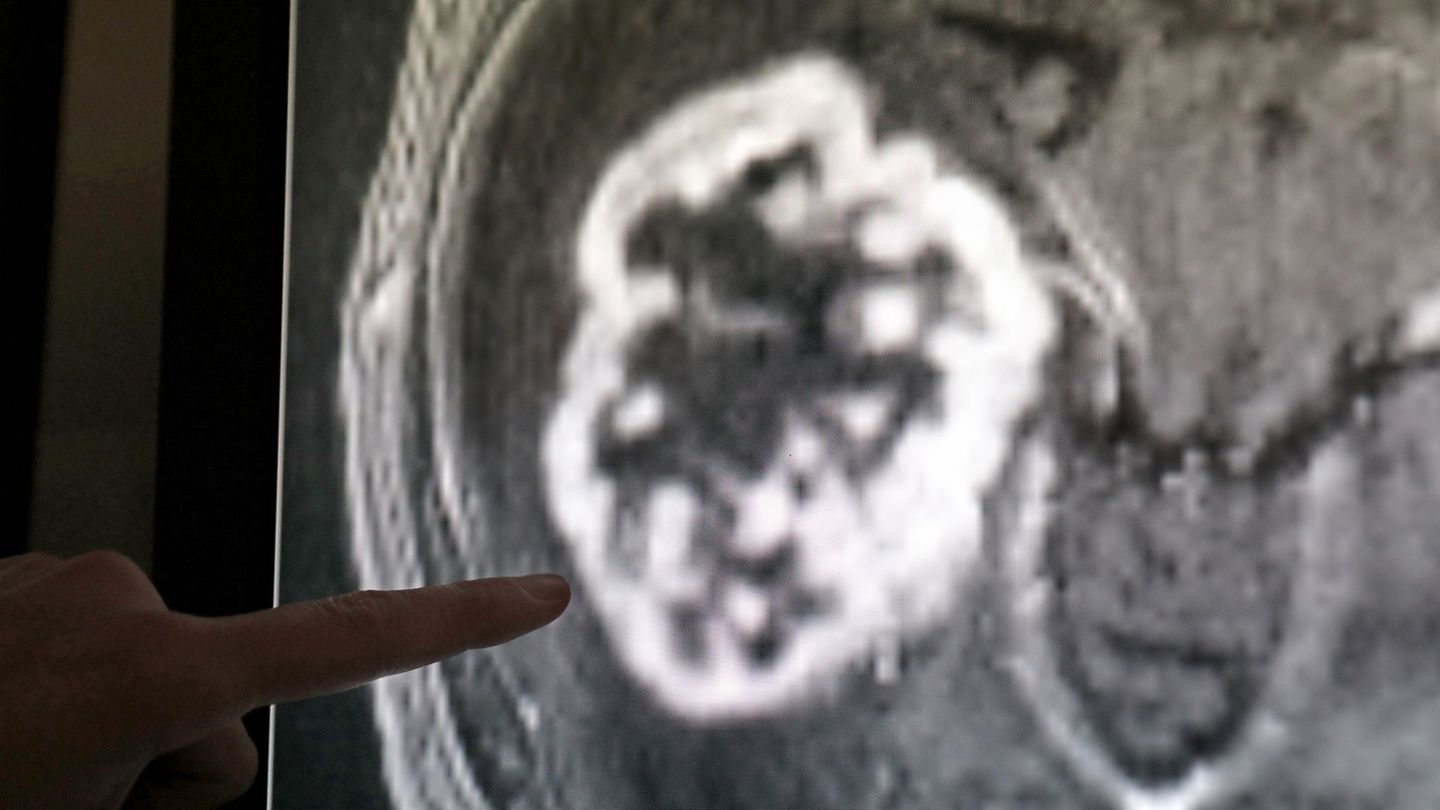

Mehr als 8.000 Sachsen-Anhalt sind 2024 an Krebs gestorben. (Symbolbild) Foto: Bernd Wüstneck/dpa-Zentralbild/dpa

Mehr als 8.000 Sachsen-Anhalt sind 2024 an Krebs gestorben. (Symbolbild) Foto